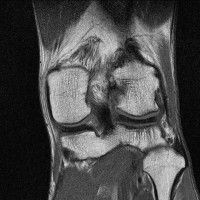

무릎 mri 간단히 봐주실 수 있으시나요 ㅠㅠ

안녕하세요 8년전 십자인대 수술하고 최근 무리한 운동에 무릎 불편감이 생겨서

mri 찍었습니다.

진단결과는 첫 찍은 병원에서 활액막염 이라는 진단을 받았습니다. 혹시 봐주실 수 있으실까요?

올라온 MRI가 단편적이라서 정확한 진단에 어려움이 있지만 십자인대에는 큰 이상이 있지는 않은것 같으며, 무릎관절내 물이 있는 것으로 보아 활액막염의 진단이 맞을 것 같습니다.

하지만 단편적인 영상이기 때문에 촬영병원에서 정확한 판독지 등을 받으시는 것이 좋겠습니다.